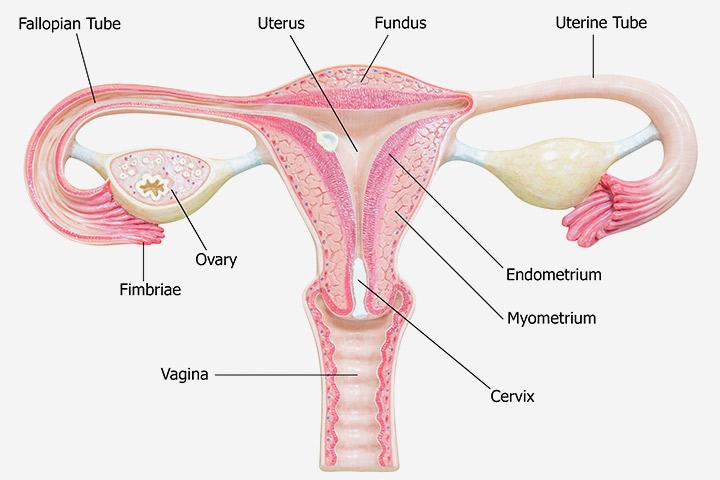

Endometrial Thickness Radiology Reference Article .

Endometrial Thickness Radiology Reference Article .

Uterine Wall Fluzo Info .

Endometrial Thickness What Is Normal And How To Measure .

Endometrial Thickness Radiology Reference Article .